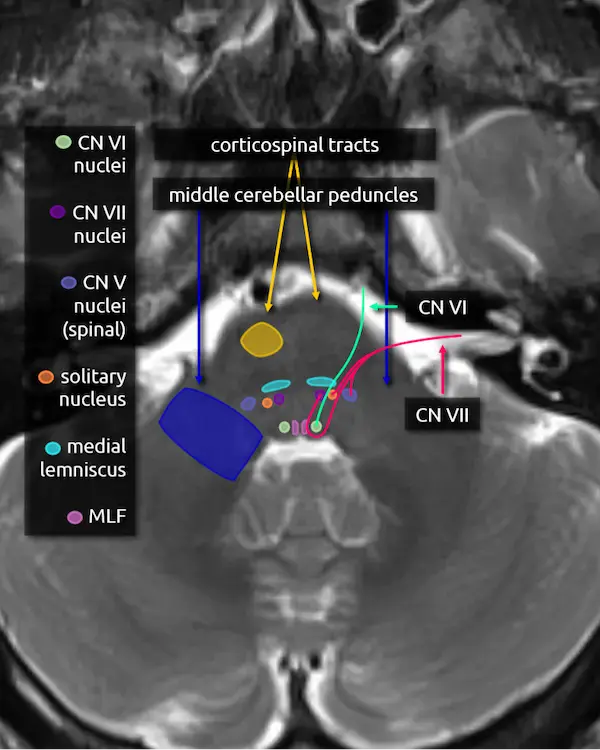

Predicting deficits of a pontine lesion

You now know enough pontine anatomy to predict the most likely symptoms for a lesion anywhere in the majority of the pons. See the figure on the right for a simplified but practical way of conceptualizing this anatomy.

Lesions in the anterior aspect of the pons are likely to damage the corticospinal and corticobulbar tracts, producing weakness or paralysis. Lesions in the center of the pons are likely to damage the transverse pontine fibers, causing ataxia. Remember that the corticopontocerebellar pathway makes up a large part of those fibers. Lesions towards the back of the pons are likely to involve the medial lemniscus and spinothalamic tract, producing sensory deficits. Lesions that involve the most posterior aspect of the pons surrounding the fourth ventricle are likely to cause diplopia due to damage to the MLF and/or the abducens nerve (CN VI), depending on the level.